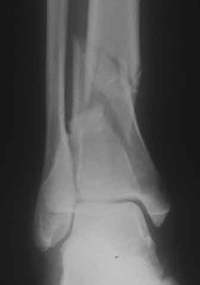

Unfallaufnahme (ap)

Offene Tibiafraktur Grad III